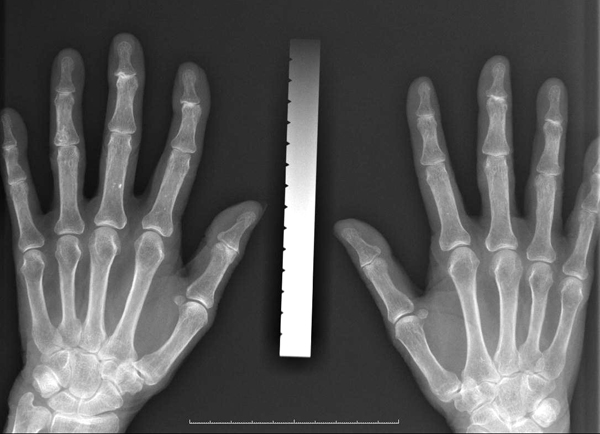

○骨塩定量(骨密度)検査

現在、我が国の骨粗鬆症の患者は1000万人ともいわれていますが、女性がそのうちの8割を占めており、また、60歳代の女性の約半分が骨粗鬆症だといわれています。骨塩定量(骨密度)検査とは、X線や超音波を使って、骨の中に詰まっているカルシウムなどのミネラル成分の量を測定することです。

測定方法はいくつかありますが、当クリニックでは、人差し指にX線を当て、手の骨と厚さの異なるアルミニウム板とを同時に撮影し、骨とアルミニウムの濃度を比較することによって骨密度を測定するDIP法を採用しています。検査が短時間で済むので、スクリーニングに適しています。